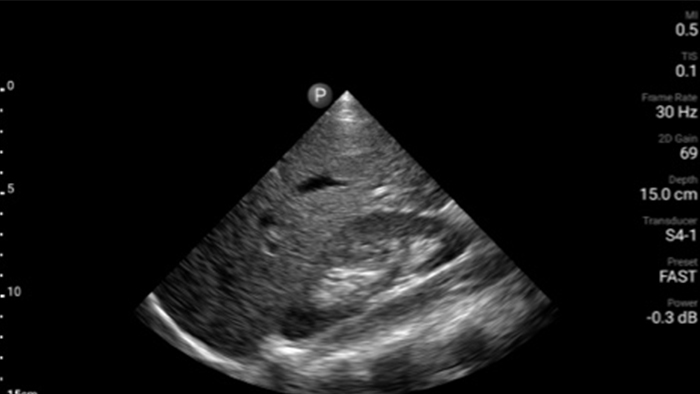

Actúe más rápido para proteger el corazón de sus pacientes

Cuando los segundos cuentan, el ultrasonido portátil puede marcar la diferencia. Lumify puede proporcionar las imágenes de alta definición que requiere cuando y donde las necesite.

Transductor de disposición en fase de banda ancha Lumify S4-1

Oportunidad de revertir potencialmente la miocardiopatía

Introducción a la ecocardiografía transtorácica